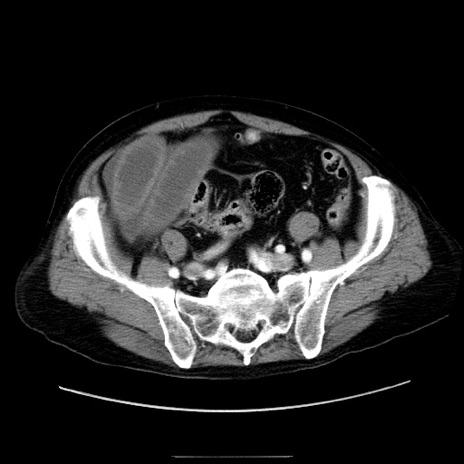

症例30(横断像)

【症例】80歳代男性

【主訴】臍周囲痛

【現病歴】約6時間前から臍下部痛が出現。次第に腹部膨隆・背部痛も生じてきたため来院。背部痛の場所は変化しない。

【既往歴】腎盂腎炎

【身体所見】意識清明、BT 36.3℃、BP  131/87mmHg、P 87bpm、SpO2 100%(RA)、臍周囲自発痛・圧痛あり、反跳痛なし、自発痛部位に一致して板状硬あり、腹部膨隆、腸雑音減弱、CVA tenderness両側陰性。

【データ】WBC 19600、CRP 0.33